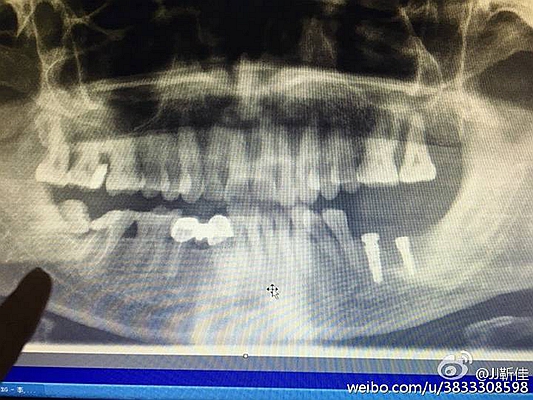

種入植體

今年的額外牙真多啊 男孩14周。

術(shù)后拍片